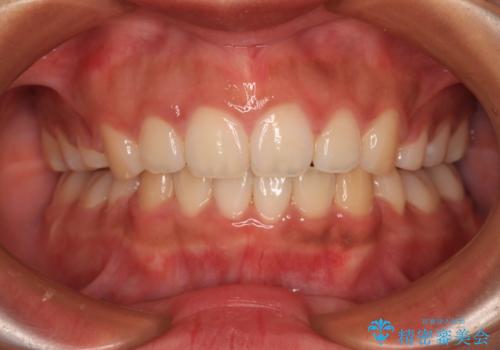

左右の臼歯は、当初1歯対1歯の咬合でしたが、終了時には理想とされる1歯対2歯に改善させることができました。

治療途中ではオープンバイトになってしまう局面もあるほど、患者様の気になっていたディープバイトをしっかりと改善することができました。

ディープバイトの改善により就寝中の食いしばりも改善され、患者様には大変満足していただきました。